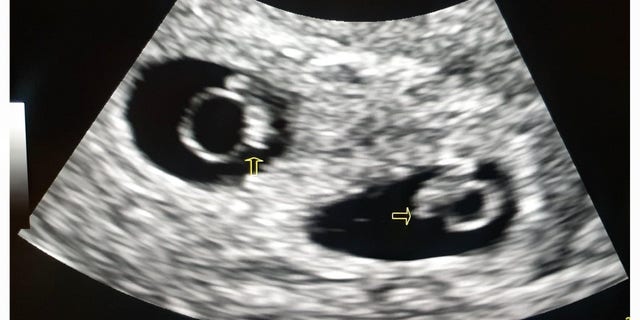

While still in labor, Shakina was transferred and admitted to Mount Sinai Hospital, about an hour-and-a-half drive away, one day later at 21 weeks and six days. Miraculously, the twins were born just one hour after they turned 22 weeks gestation.

Both Adiah and Adrial weighed less than a pound each and were successfully resuscitated. Along the way, the children had several complications from brain bleeds, bowel perforations and lung disease from prematurity. Several near-death experiences terrified Shakina and Kevin and left their twins' medical team uneasy.